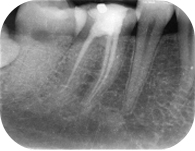

根管治療就是俗稱的抽神經,但其實除了抽牙髓神經之外,還必須要把牙根內的管路清創乾淨,擴大後並封填起來,才算是一個完整的療程。治療的過程中,常常需要拍攝數次的根尖X光片,確定根管的方向數量與治療品質,無須擔心劑量的問題,牙科的劑量遠遠低於胸腔X光的劑量。

根據統計,大臼齒做過根管治療,沒有套起來的,五年內發生問題的機率高達80%,而前牙發生問題的機率是 20%,因此提供這數據給大家,您要不要冒風險呢,聰明的讀者就自行決定了,畢竟是自己的牙齒,萬一裂掉的話,風險自己負責唷!